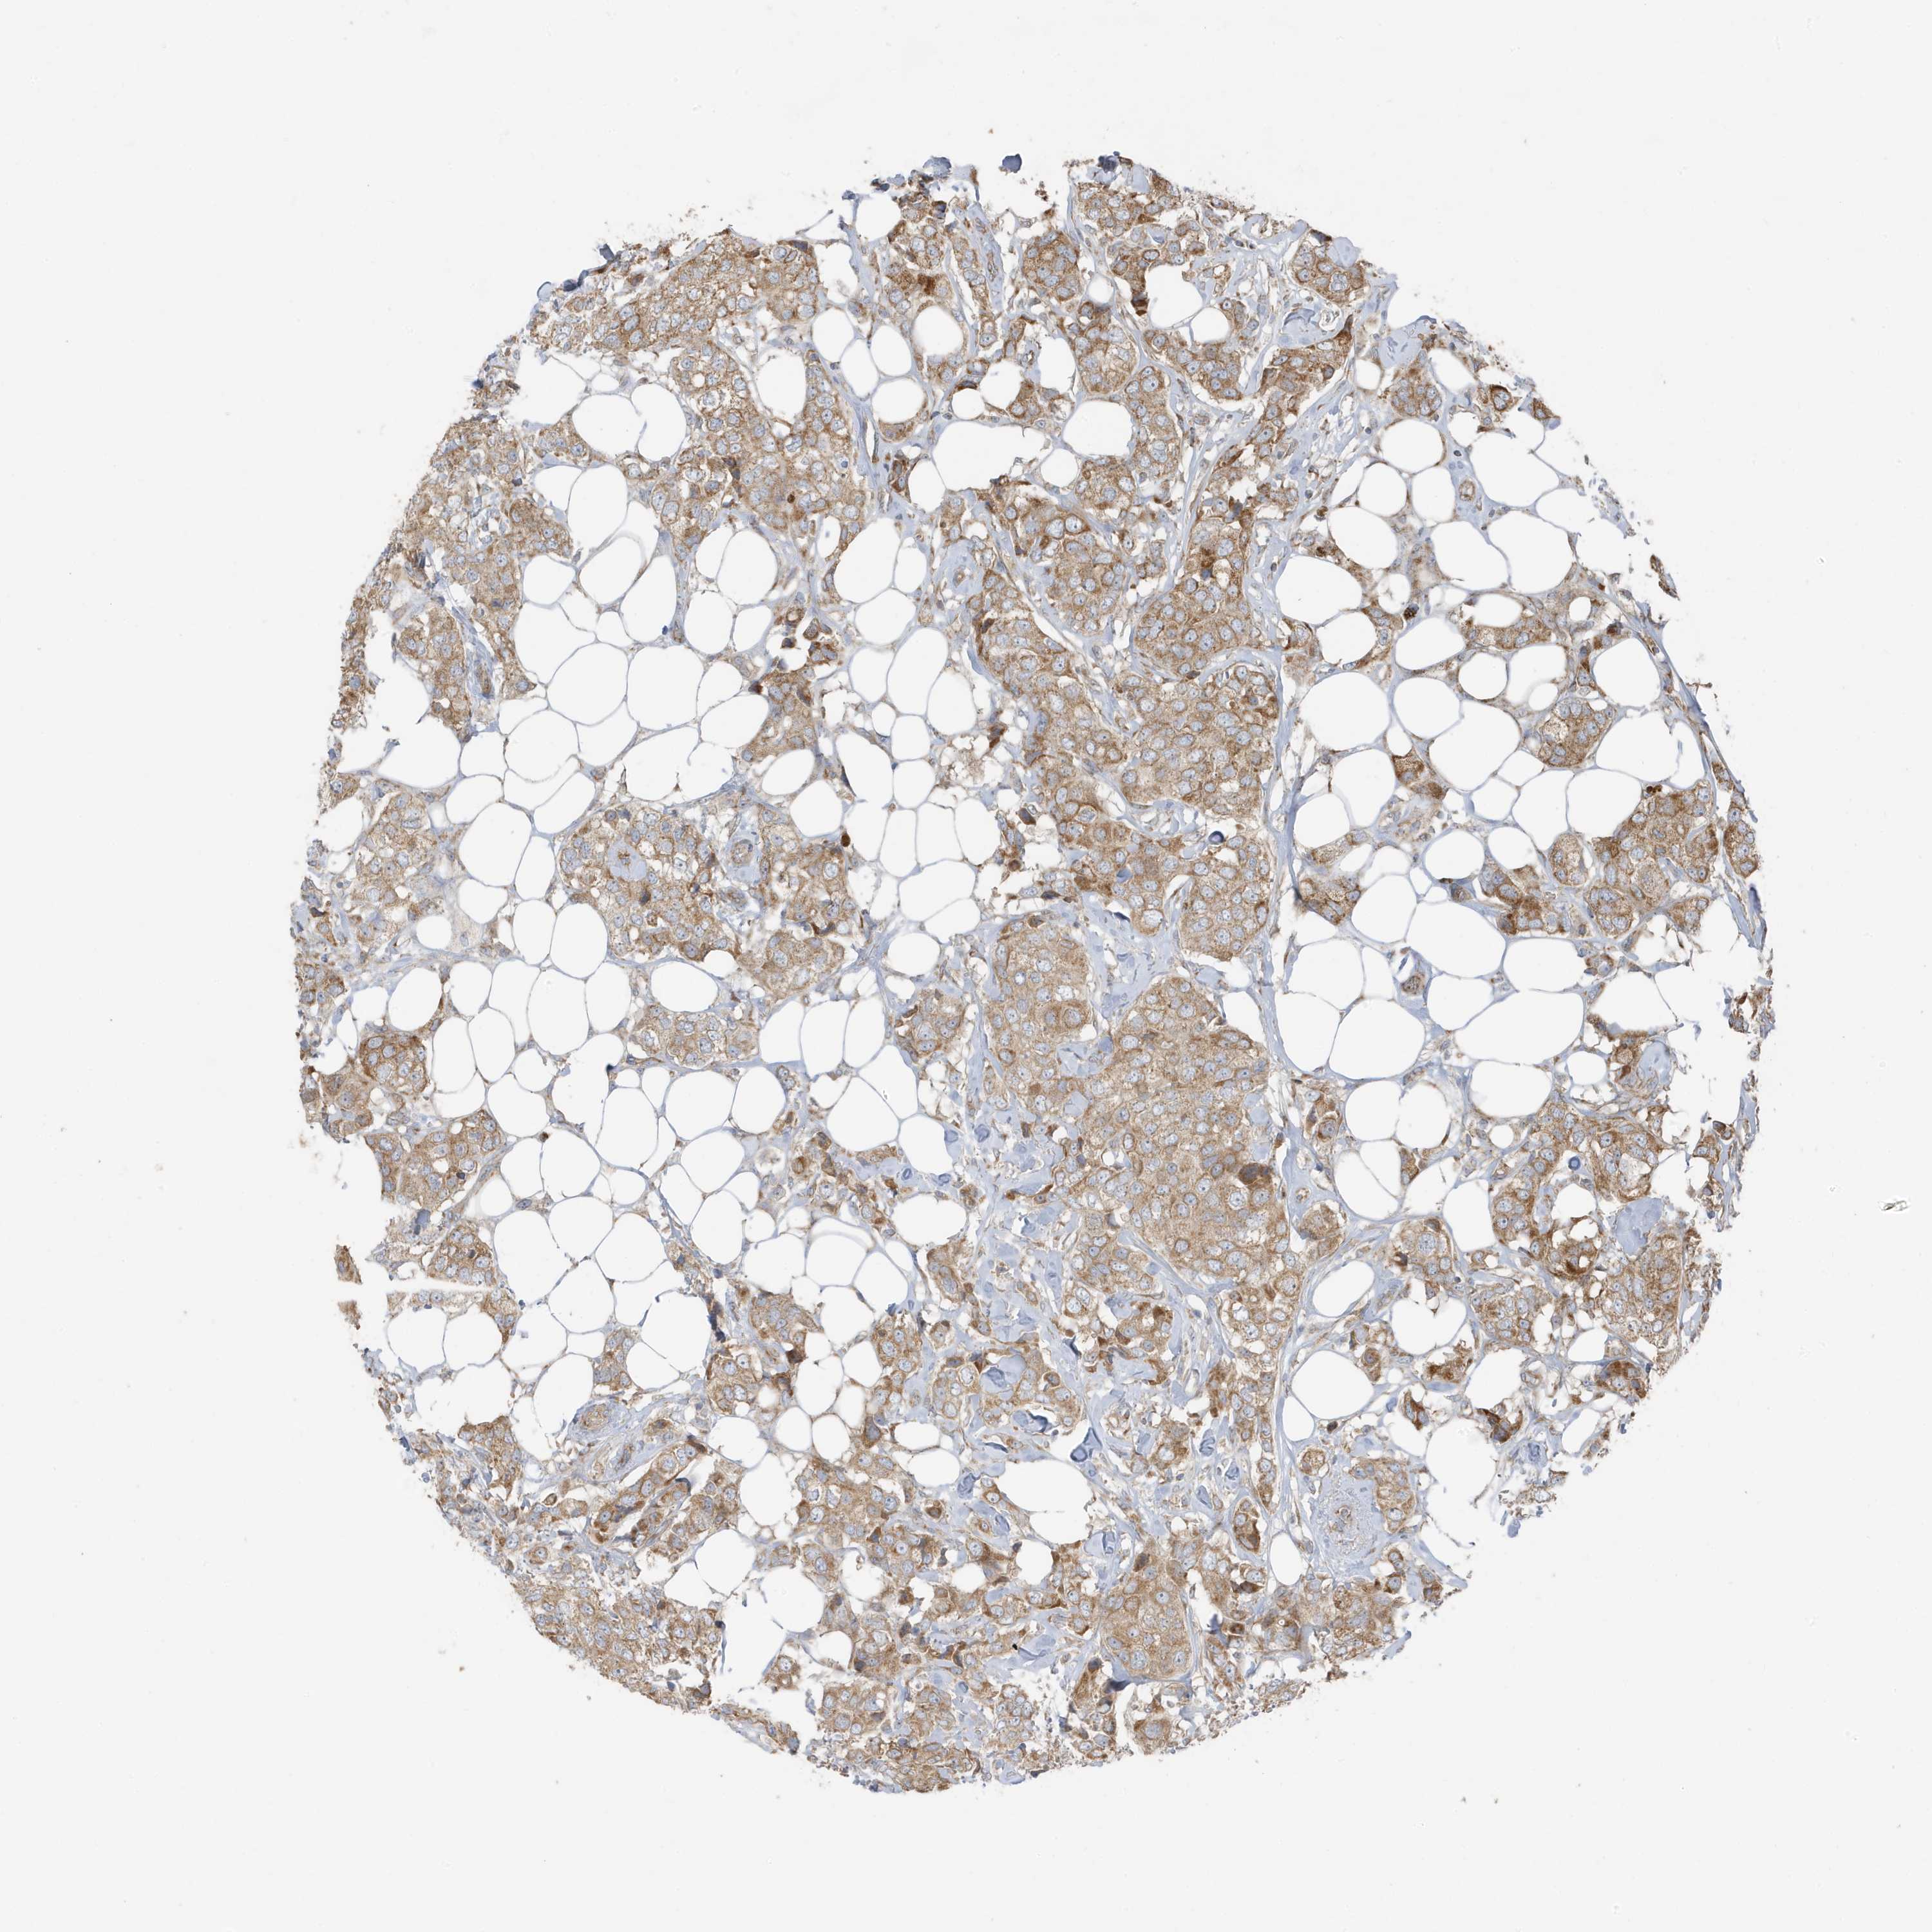

CANCER BREAST CANCER Show tissue menu

BRCA TCGA BRCA VALIDATION PROTEIN EXPRESSION